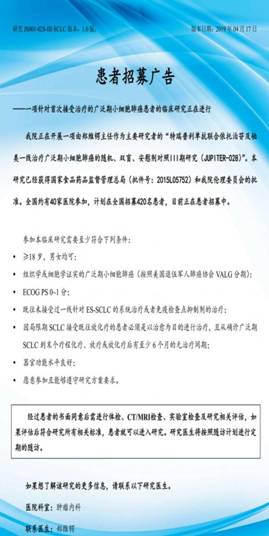

目前我科已对接了多个国内、国际多中心药物临床试验,主要集中在免疫、抗血管生成、多靶点小分子TKI抑制剂等新药,涵盖卵巢癌、结直肠癌、小细胞肺癌等多个瘤种,为肿瘤初治或者是多线治疗失败的患者提供更多治疗选择,提高疗效的同时可大大减轻患者的经济负担。

下图为我科对接临床试验的具体入组要求,如有需求可携带相关资料赴肿瘤内科门诊了解。